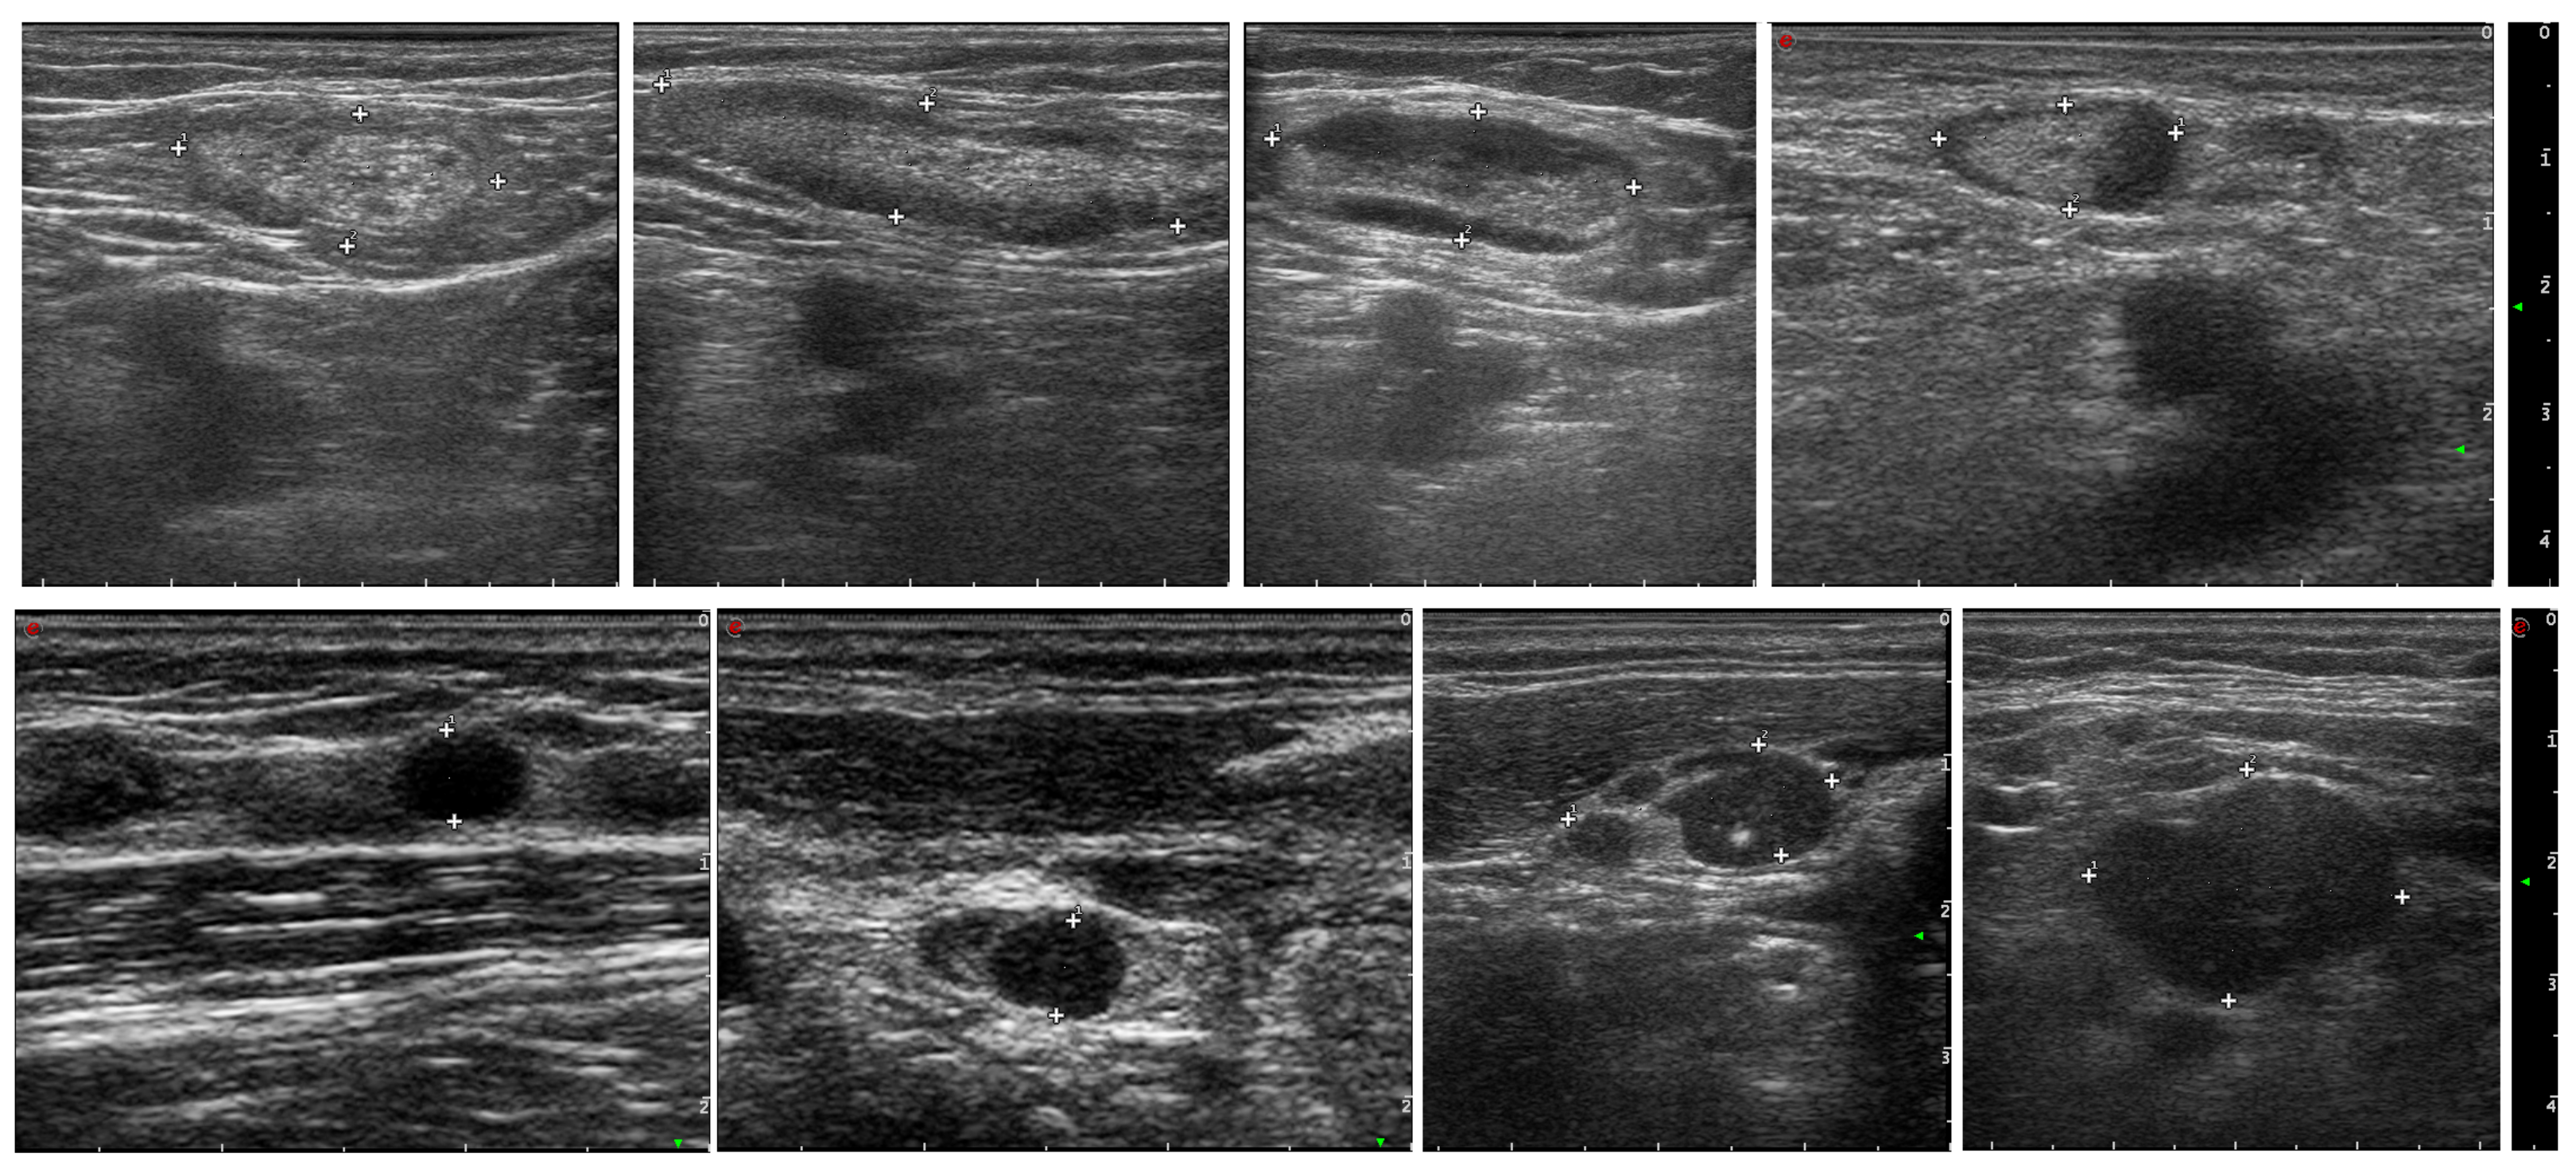

Example USG images of LNs for both cancerous and non-cancerous cases are presented in Figure 2. Ultrasound imaging is a non-invasive diagnostic technique that uses high-frequency sound waves to produce images of structures within the body. In these images, the LNs are marked with plus signs (+) to outline their borders and dimensions.

The malignant LNs depicted in the bottom row show different characteristics:

• They may be larger in size.

• The shape can be more irregular or rounded rather than oval.

• The internal structure appears more heterogeneous with less clear differentiation between the cortex and hilum.

• They may show signs of infiltration to the surrounding tissues.

These images are used by healthcare professionals to aid in the diagnosis and staging of LN involvement in cancer. The evaluation of the sonographic characteristics of LNs is essential in oncology for treatment planning and prognosis.

Figure 2. Example USG images of lymph nodes, representing benign (upper row) and malignant cases (bottom row).